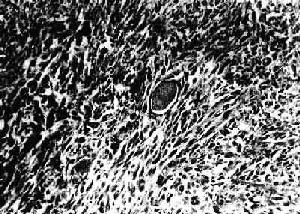

肺的纖維肉瘤肉眼見腫瘤為局限性分葉狀硬固結節,切面呈黃褐色或灰白色。位於皮膚,很少侵及深部組織。在同一腫瘤內,組織學表現並不相同。但通常可找到不典型病變,其中成纖維細胞產生網狀纖維,而膠原纖維排列成鏇渦狀或車輪狀,核有絲分裂象少,膠原纖維不多,血管比較豐富,偶見“黃瘤細胞”,真皮乳頭往往受腫瘤侵犯,表皮及附屬器萎縮。細胞的多少及異形程度在腫瘤的不同部位變異很大,有些部位可全部為纖維硬化性。核有絲分裂少見。通常向周圍擴大。復發者更不規則,為多髮結節,比原發者細胞成分多,可以看不到典型緻密的車輪狀結構,大都呈粘液瘤樣。